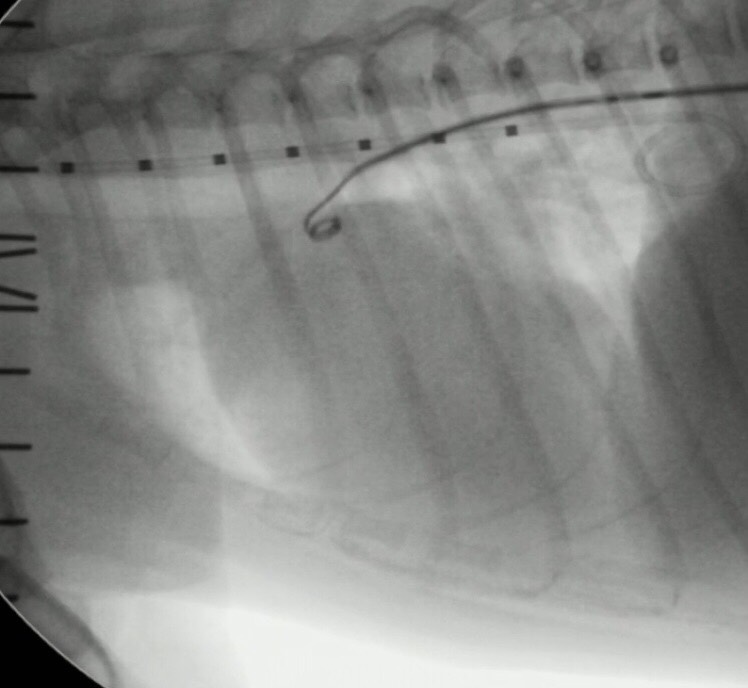

犬に動脈管開存症に対して心臓カテーテル手術を行なった症例

今回は健康診断で、心雑音が聴取され、各種検査で動脈管開存症と診断し心臓カテーテルでの手術を実施した症例を紹介させて頂きます。

今回、治療法としてコイル塞栓術を実施いたしました。

写真は、コイル塞栓の一連の流れを掲載させて頂きました。

症例は術後の短絡血流もなく無事に退院できました。